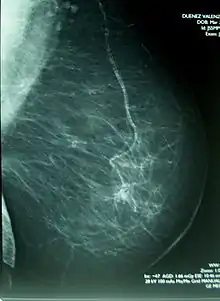

Mamografía

La mamografía o mastografía consiste en una exploración diagnóstica de imagen por rayos X de la glándula mamaria, mediante aparatos denominados mamógrafos (en dosis de alrededor de 0,7 mSv). Estos aparatos disponen de tubos de emisión de rayos X especialmente adaptados para conseguir la mayor resolución posible en la visualización de las estructuras fibroepiteliales internas de la glándula mamaria.

La capacidad de identificación de lesiones de mínima dimensión ha preconizado la utilización de la mamografía en revisiones sistemáticas para detectar tumores antes de que puedan ser palpables y clínicamente manifiestos (cribage mamográfico). Este diagnóstico, efectuado en una fase muy precoz de la enfermedad, suele asociarse a un mejor pronóstico de curación, así como a la necesidad de una menor agresividad del tratamiento para el control del cáncer.

Los radiólogos usan un método estándar para interpretar y comunicar los resultados de la mamografía, que actualmente se considera el idioma universal en el diagnóstico de la patología mamaria. Cuando detectan una lesión sospechosa de cáncer, la clasifican dentro de una categoría de BI-RADS (Breast Imaging-Reporting and Data System), las primeras etapas I y II son benignas, la III es probablemente benigna, mientras la IV y V aumenta la probabilidad de que sean malignas. Este sistema permite estandarizar la terminología del informe mamográfico y categorizar las lesiones estableciendo el grado de sospecha y asignar la actitud a tomar en cada caso. En muchas ocasiones la mamografía puede revelar lesiones malignas sin que estas se palpen clínicamente.[9][10]